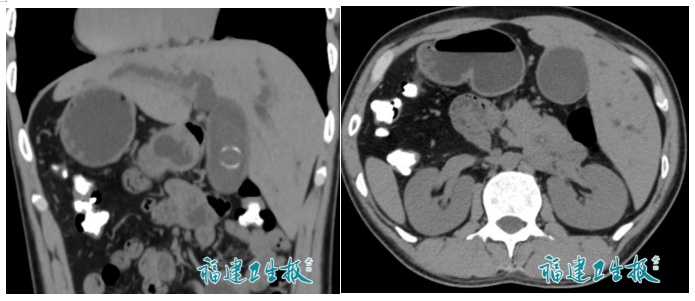

陈先生因腹痛、皮肤发黄前往医院检查,检查结果令人意外:不仅查出有胆总管结石,更惊人的是,他的右位心、完全内脏反位,通俗说,就是“五脏六腑像照镜子一样长反了”!

反转的脏器CT影像